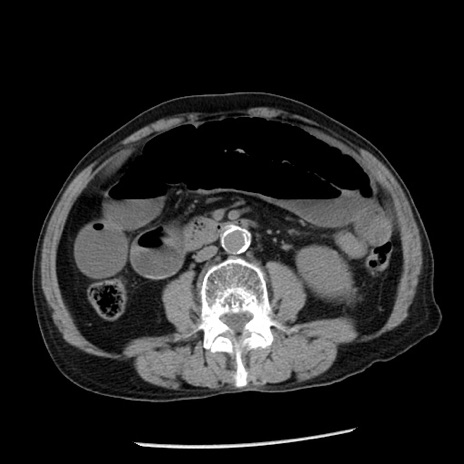

冠状断像

【症例】80歳代男性

【主訴】嘔吐

【現病歴】昨晩2回嘔吐あり、今朝になっても嘔吐あり。来院。

【既往歴】胃潰瘍

【身体所見】意識清明、BT 37.6℃、BP 166/95mmHg、HR 100bpm、SpO2 97%、腹部:平坦・軟、腸蠕動音聴取良好、圧痛なし。

【データ】WBC 21900、CRP 1.46